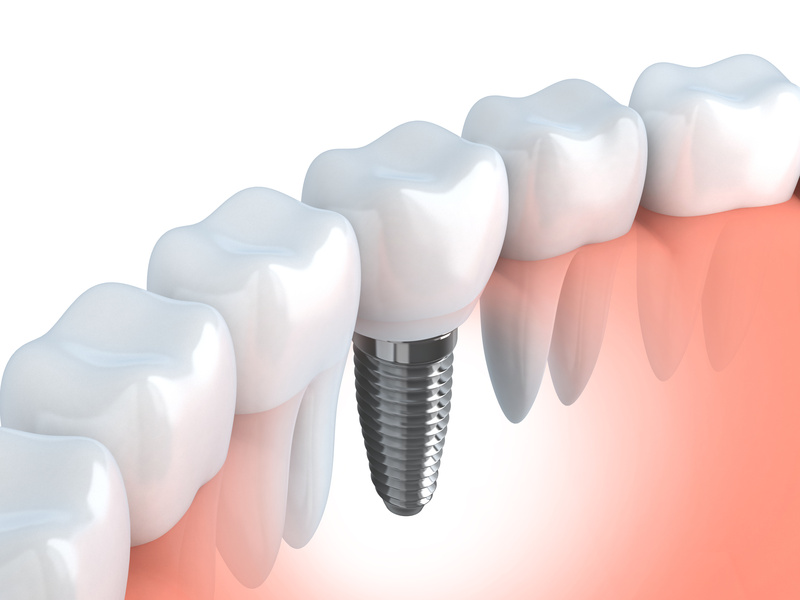

Pojavom zubnih implanta, do sada nezamjenljive metalokermičke krunice, mostovi i proteze odlaze u prošlost. Danas implanti potupno mjenjaju filozofiju stomatologije, postavši neizbježna metoda rekonstrukcije izgubljenih zuba.

Posljednjih godina broj pacijenata,koji se umjesto klasičnih krunica i mostova odlučuju za implante,se drastično povećava. Prije par godina mostovi su bili u prednosti, zbog toga sto se implanti nisu mogli ugrađivati kod pacijenata čije su vilice ostale bez koštane mase. Ali,nove tehnologije u oralnoj hirurgiji su omogućile ugradnju vještačke kosti u atrofiranim vilicama, čime su implanti dobili na prednosti u odnosu na mostove.

Na taj način zubni implant u potpunosti zamjenjuje izgubljeni zub. Implant postaje replika nekadašnjeg zuba. Procedura za implantiranje zuba je jednostavna. Na početku potrebno je izvršiti rendgensko snimanje vilice, kako bi se utvrdilo da li ima dovoljno koštane mase u vilici. Ako nema, pre implantiranja vrši se operacija ugradnje vještačke kosti. Sama operacija ugradnje implantata traje oko 30 minuta. Nakon završene operacije čeka se 3 mjeseca da implant uraste u viličnu kost. Tek nakon tog perioda pacijent dolazi ponovo u ordinaciju gdje mu se na implant fiksira nadograđena struktura (supra struktura) i vrši izrada protetskih nadoknada (krunica).